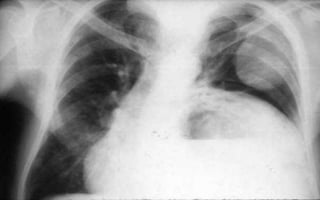

CASOS PATOLOGICOS

1. Marcado aumento del

índice cardiotorácico.

2. La punta del corazón

se dirige al diafragma

por dilatación

biventricular.

3. Aumento del tamaño

de la aurícula derecha.